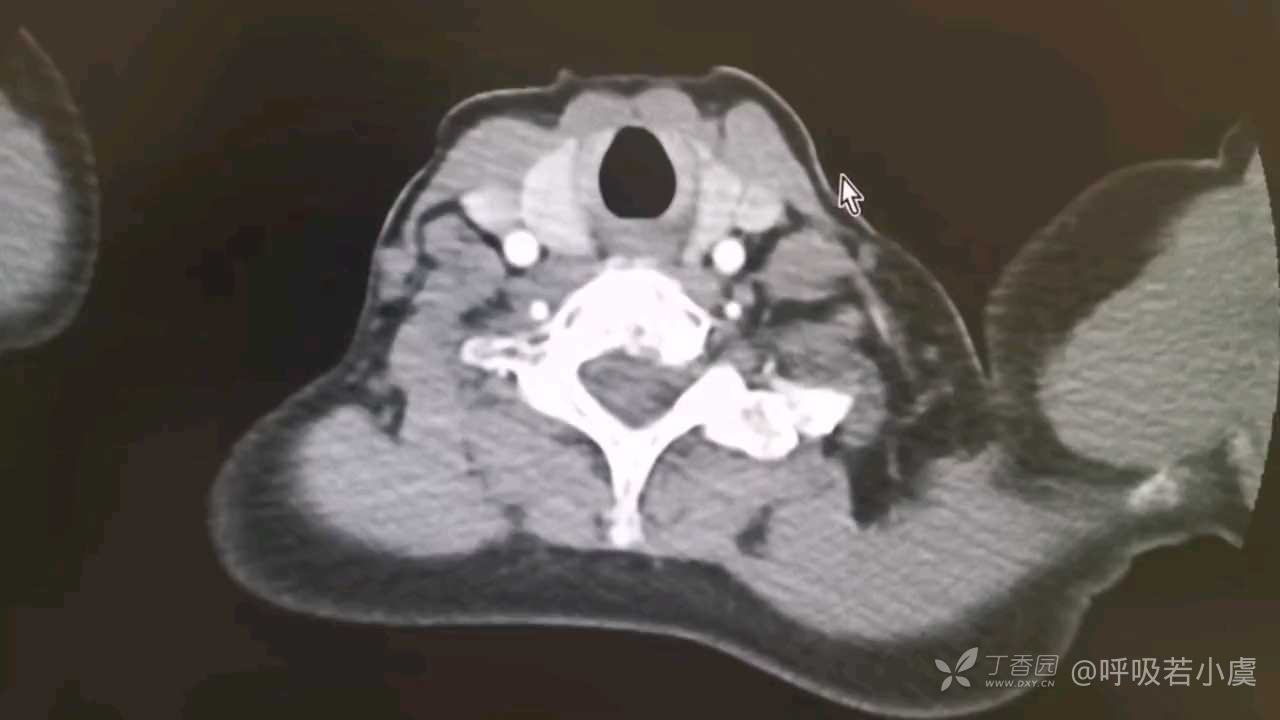

病例肺CT基础:凝固性坏死和液化性坏死的鉴别诊断